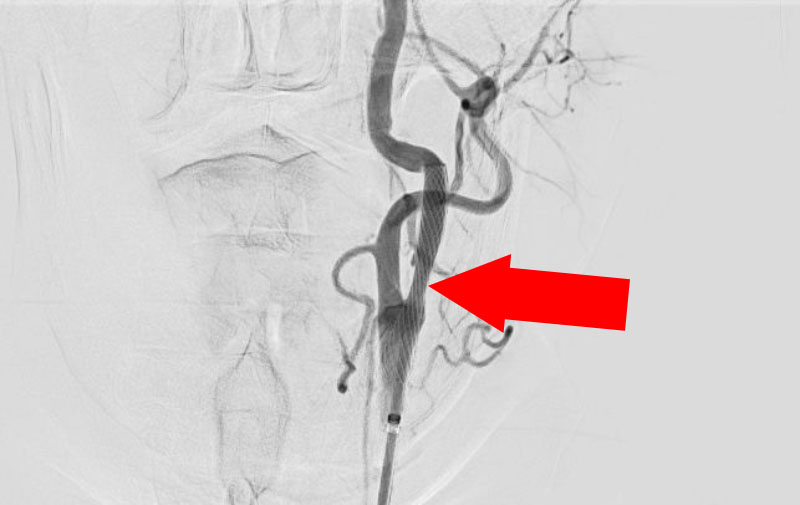

左頚部内頚動脈狭窄症

手術前1

手術前2

手術中1

手術中2

手術後1

手術後2